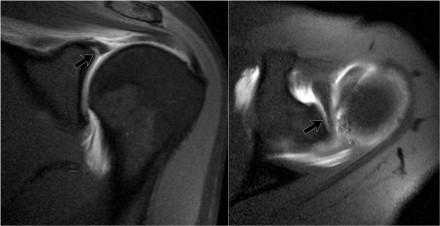

Варианты строения суставной губы

Существует много вариантов строения суставной губы.

Эти вариатны нормы локализуются в области 11-3 часов.

Важно уметь распознавать эти варианты поскольку они могут симулировать SLAP-повреждения.

За повреждение Банкарта, эти варианты нормы обычно не принимают, поскольку оно локализуется в позиции 3-6 часов, где анатомические варианты не встречаются.

Однако повреждение суставной губы может возникать в области 3-6 часов и распространяться на верхние отделы.

Подгубное углубление

Есть 3 типа прикрепления верхних отделов суставной губы в области 12 часов, в месте прикрепления сухожилия длинной головки двуглавой мышцы плеча.

I тип - между суставным хрящем суставной впадины лопатки и суставной губой нет углубления

II тип - есть маленькое углубление

III типа - есть крупное углубление

Это подгубное углубление тяжело отличить от SLAP повреджения или подгубного отверстия.

Подгубное отверстие

Подгубное отверстие - отсутствие прикрепления передневерхних отделов суставной губы в области 1-3 часов.

Определяется у 11% населения.

При МР-артрографии подгубное отверстие не должно приниматься за подгубное углубление или SLAP-поврежедение, которые также локализуются в данной области.

Подгубное углубление расположено в области прикрепления сухожилия двуглавой мышцы плеча на 12 часов и не распространяется на область 1-3 часов.

SLAP-повреждение может распространятся на область 1-3 часов, но всегда должно быть вовлечено прикрепление сухожилия двуглавой мышцы.

Пролистывайте изображения и обратите внимание суставная губа не прикреплена в области 12-3 часа, в области подгубного отверстия.

Обратите внимание гладкие края, в отличии от SLAP-повреждения.